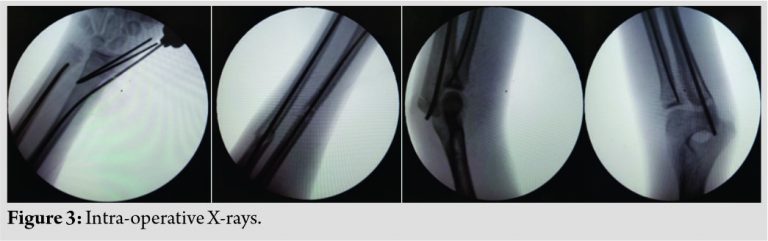

Surgery was performed without a tourniquet. The open wound was thoroughly debrided and irrigated. The ulnar fracture was managed with close reduction and internal fixation with titanium elastic nail (TENS). Distal radius was managed by percutaneous fixation with two K-wires under the guidance of image intensifier, while the shaft of radius fracture was managed by close reduction and internal fixation with elastic TENS nail with a lateral entry point [Fig. 3].